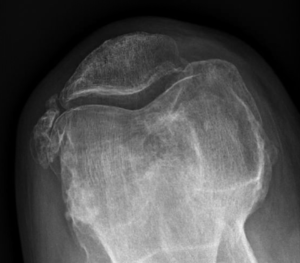

Le diagnostic repose sur un faisceau d’arguments cliniques (interrogatoire, examen physique) et sur l’imagerie (pincement de l’articulation, présence d’ostéophytes ou « becs » osseux). Lorsque ces signes sont présents, il n’est pas nécessaire d’effectuer d’autres examens à visée diagnostique que la radiographie standard.

Lorsque l’usure du genou atteint 2 ou 3 compartiments (gonarthrose tricompartimentale) (Fig.7)

a échoué, la seule solution chirurgicale est la prothèse totale du genou. Elle consiste à remplacer les 2 compartiments fémorotibiaux (interne et externe), avec ou sans remplacement de la rotule (resurfaçage).